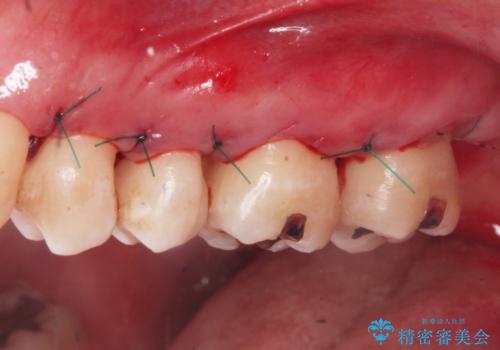

3. 縁下歯石のクリーニングの治療後